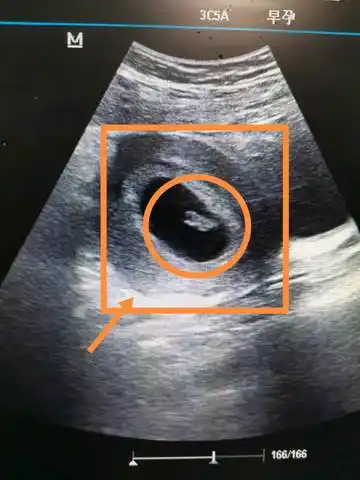

热乎乎的胎心胎芽来了,医生说长的挺好的,安安心心的养胎啦!